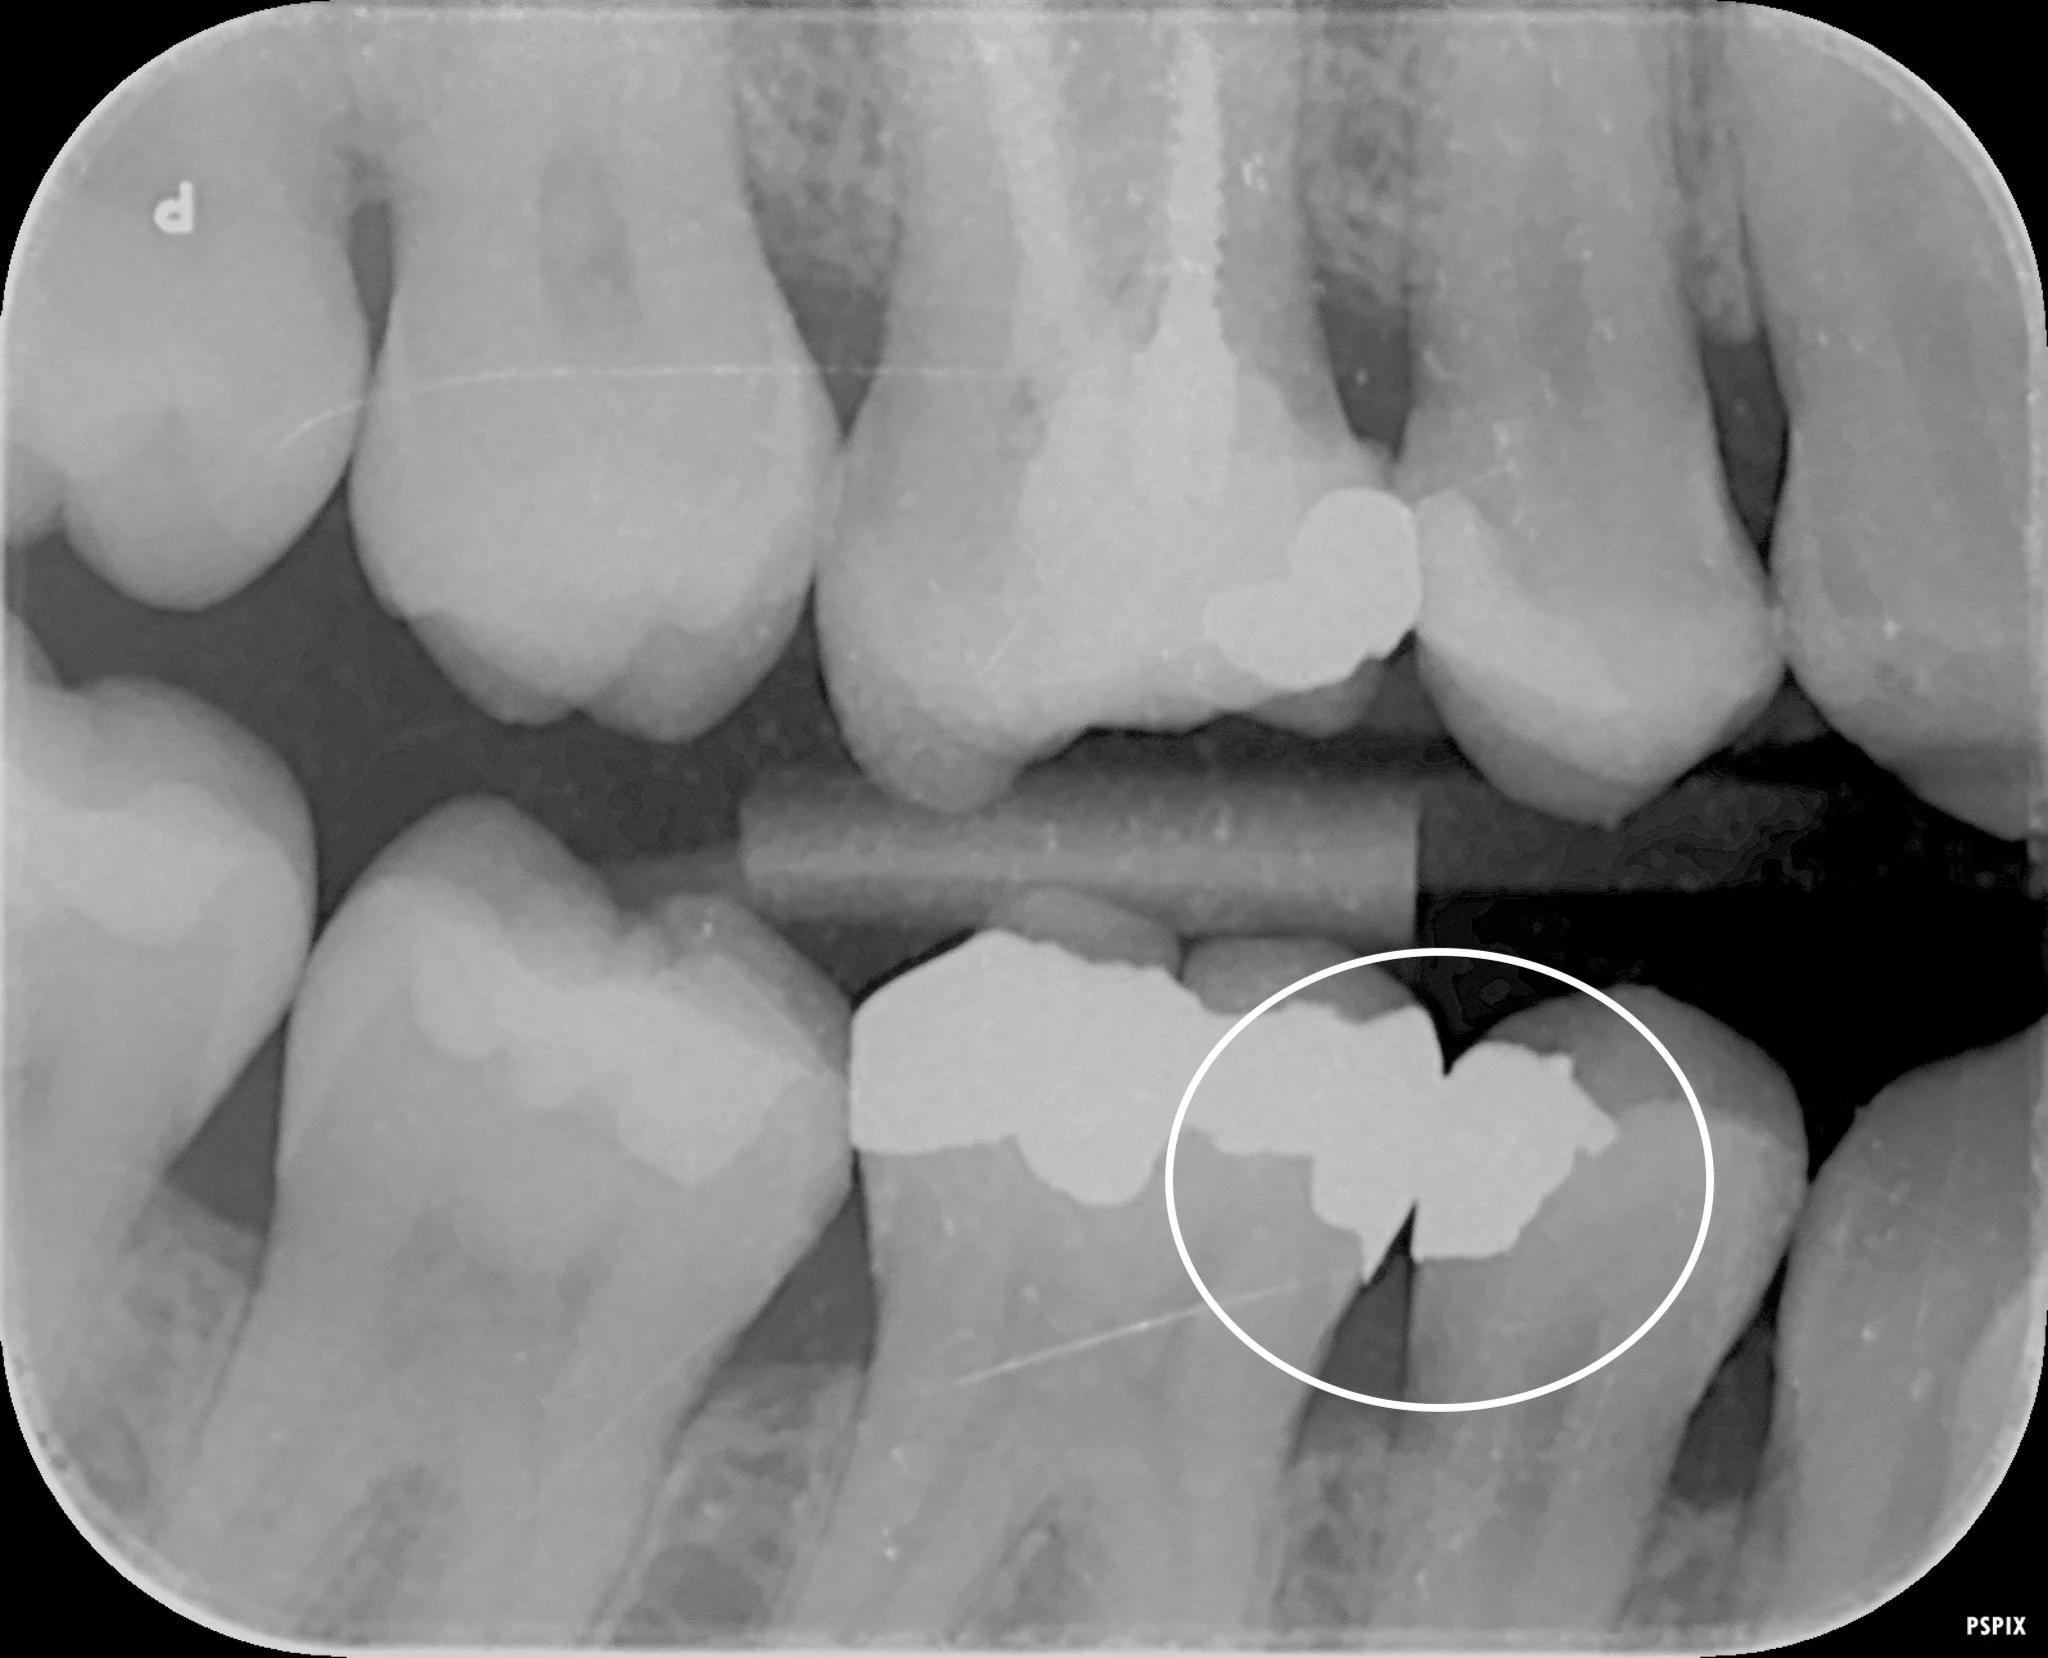

An x-ray showing a big overhanging filling

What Are Overhangs and Rough Margins?

An overhanging filling is exactly what it sounds like. It’s when part of the filling extends beyond the natural shape of the tooth, usually into the space between two teeth or slightly under the gum.

Instead of a smooth transition, you end up with a small ledge or lip that shouldn’t be there.